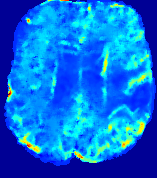

4.2.1 Advection Imaging via Advection

Slice #1Slice #2Slice #3Slice #4Slice #5Slice #6𝐕gt2subscriptnormsuperscript𝐕gt2\|{\bf{V}}^{\text{gt}}\|_{2}Refer to captionRefer to captionRefer to captionRefer to captionRefer to captionRefer to caption(a)Refer to captionRefer to captionRefer to captionRefer to captionRefer to captionRefer to caption(b)Refer to captionRefer to captionRefer to captionRefer to captionRefer to captionRefer to caption(c)Refer to captionRefer to captionRefer to captionRefer to captionRefer to captionRefer to caption(d)Refer to captionRefer to captionRefer to captionRefer to captionRefer to captionRefer to caption(e)Refer to captionRefer to captionRefer to captionRefer to captionRefer to captionRefer to caption(f)Refer to captionRefer to captionRefer to captionRefer to captionRefer to captionRefer to captionRefer to caption000.30.30.30.60.60.60.90.90.91.21.21.21.51.51.5(mm/s)𝑚𝑚𝑠(mm/s)

Figure 12: PIANO effectiveness and robustness testing: advection imaging via advection. Top row shows the ground truth 𝐕gt2subscriptnormsuperscript𝐕gt2\|{\bf{V}}^{\text{gt}}\|_{2} used for simulating pure advection. (a)-(f) refer to the results for 𝐕2subscriptnorm𝐕2\|{\bf{V}}\|_{2} estimated by PIANO, with simulated advection imaging series where Rician noise at levels 0%, 2%, 4%, 6%, 8%, 10% was added respectively.

Our goal here is to determine if PIANO can estimate a known velocity field from a concentration time-series consistent with this velocity field. To this end, for each patient in the ISLES 2017 training set, we treat the velocity field estimated by PIANO as the ground truth velocity field (𝐕gtsuperscript𝐕gt{\bf{V^{\text{gt}}}}), and the first image in the concentration time-series dataset {Cti}superscript𝐶subscript𝑡𝑖\{C^{t_{i}}\} (as described in Sec. 3) is used as the initial condition (C0superscript𝐶0C^{0}). We then simulate ‘advection imaging’ {Cti(Ω)|i=0, 1,, 40}conditional-setsuperscript𝐶subscript𝑡𝑖Ω𝑖0140\{C^{t_{i}}\in\mathbb{R}(\Omega)|i=0,\,1,\,\ldots,\,40\}, i.e., we create a time-series of concentration images driven by the velocity 𝐕:=𝐕gtassign𝐕superscript𝐕gt{\bf{V}}:={\bf{V^{\text{gt}}}} only via the advection PDE:

We further simulate noisy concentrations by adding Rician noise [24] with variances equalling 2%, 4%, 6%, 8%, 10% of the originally simulated concentrations {Cti}superscript𝐶subscript𝑡𝑖\{C^{t_{i}}\}. We then test how well PIANO can estimate the underlying velocity field via Eq. 15 with the same model settings (except without estimating the diffusion) as in Sec. 3 given the original and the noisy concentration time-series. Fig. 12 shows the estimated 𝐕est2subscriptnormsuperscript𝐕est2\|{\bf{V}}^{\text{est}}\|_{2} for one patient. Fig. 11 (a) shows the summarized estimation results for all 43 patients. PIANO almost perfectly captures the underlying velocity field, and maintains excellent performance even when estimating from concentrations with varying noise levels.